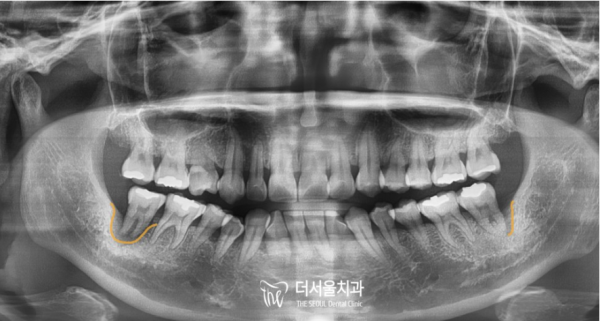

양쪽 아래 어금니가 모두 예쁘게 잘 심어진 것을 확인할 수 있습니다.

환자분께서는 저희 태평역치과 더서울치과의 디지털임플란트에 크게 만족하신 치료였습니다.

보신것 처럼 저희 더서울치과의 디지털임플란트는 적절한 위치에 임플란트의 픽스처를 잘 심을 수 있도록

컴퓨터를 통해 정확한 위치의 가이드라인을 제시해주기 때문에 안전하고 정확한 임플란트 식립이 가능하다는 장점이 있습니다.

You can see that both lower molars are beautifully planted.

The patient was very satisfied with the digital implant of Taepyeong Station Dental Clinic The Seoul Dental Clinic.

As you can see, the digital implants of The Seoul Dental Clinic help you plant the fixture of the implants in the right place

It has the advantage of being able to implant safely and accurately because it provides accurate location guidelines through a computer.